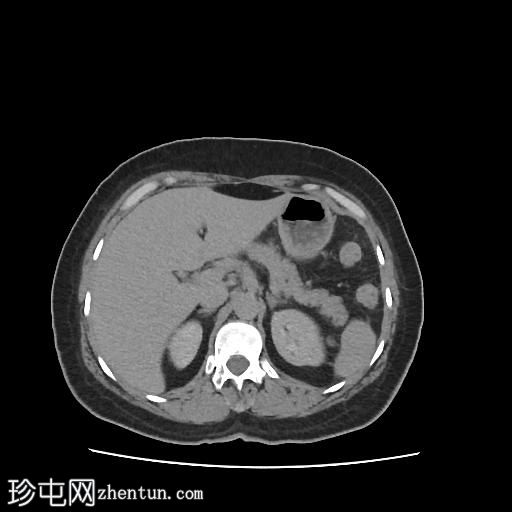

轴位增强扫描(门静脉期)

CT扫描显示:

左侧膀胱后外侧壁完全撕裂,造影剂外渗至盆腔

盆腔内可见少量积液

腹膜脂肪条索状改变,腹膜反折增厚强化,提示盆腔腹膜炎

腹腔镜

子宫切除术后医源性膀胱损伤伴盆腔腹膜炎的CT表现。